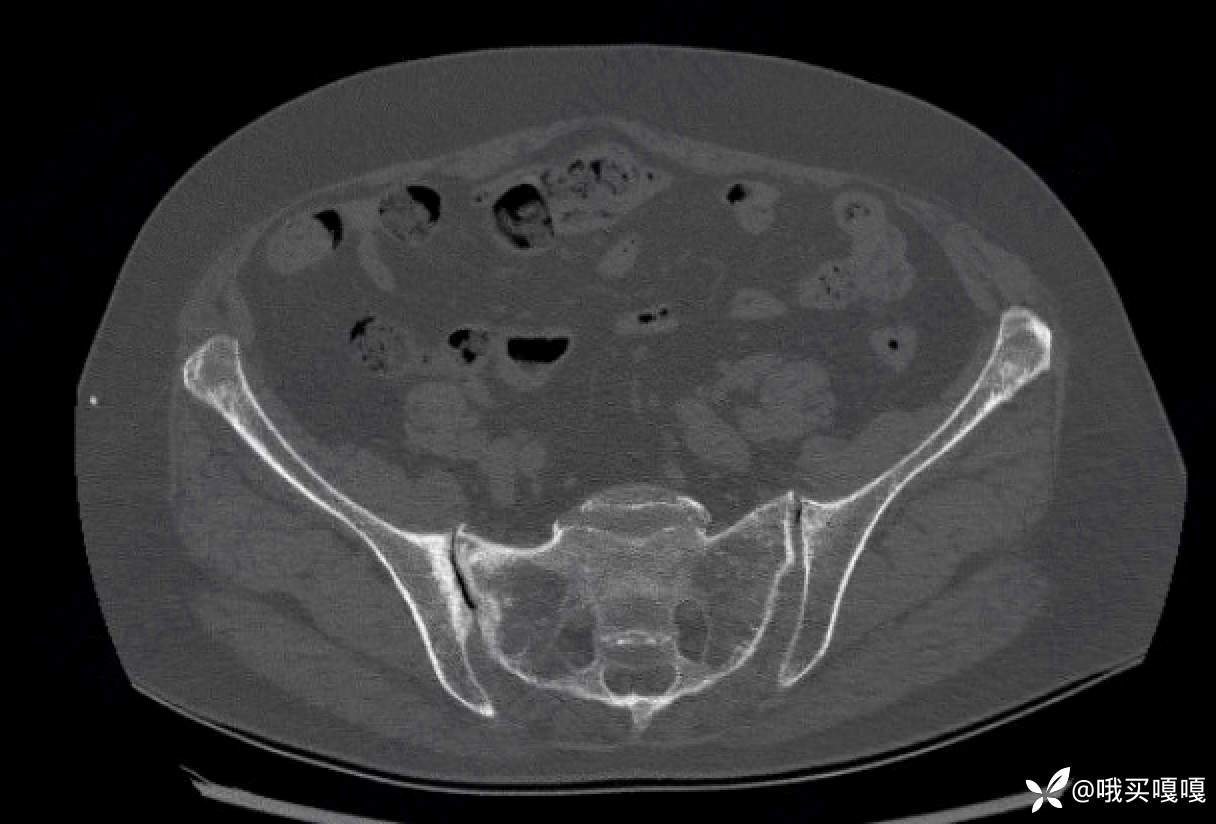

请问各位,这个骶髂关节的CT,看起来像脊柱关节炎引起骶髂关节炎的影像学改变吗?